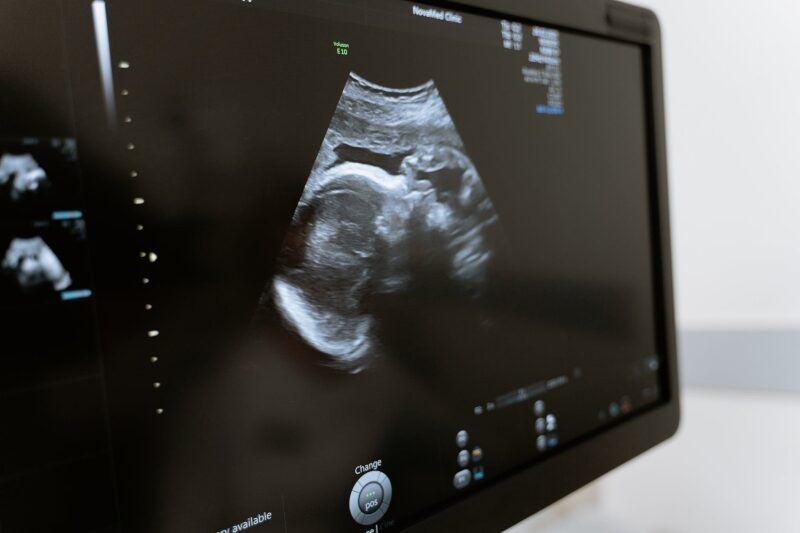

Иако трудниците не можат да го почувствуваат тоа, истражувањата покажуваат дека бебињата се подготвуваат за оваа голема активност пред да го вдишат првиот воздух. Технологии за ултразвук ни дозволуваат да погледнеме во матката и да ги набљудуваме фетусите додека сѐ уште се развиваат.

На пример, видео објавено во журналот „Архиви од болести во детството – фетална и неонатална едиција“, во 2005 година, покажува 33. неделен фетус како прави фацијални експресии кои изгледаат како плачење на ултразвукот. Откако истражувачите му дале на фетусот вибрација и стимулација со врева, тој ја отвора вилицата целосно, ја стеснува брадата и испушта три големи воздишки по ред, додека градите му се креваат, а главата му се наведнува наназад, завршувајќи со треперење на брадата. Ова движење е видено кај 10 фетуси (околу 6 проценти од целосниот број на снимени бебиња).

Тимот на Реисланд го анализирал развојот на фацијалните експресии во матката преку гледање на движењата на фетусите во второто и третото тримесечје преку 4Д ултразвучни слики – 3Д филмови од феталните акции. Овие фацијални експресии, вклучително и тоа кое може да се смета за плачење и она за смеење, Реисланд и тимот ги дефинирале во извештај објавен во 2011 година – како прекурзори на фацијалните експресии користени надвор од матката. Овие прелиминарни експресии се развиваат од 24 до 35 недела, а нивната комплексност се зголемува со гестациската возраст. Овие движења се премногу суптилни за да ги почувствува трудницата, смета Реисланд. Но, фетусот изгледа дека ги вежба барем фацијалните движења за плачење пред раѓање, подготвувајќи се да биде функционален кога ќе го земе првиот здив и ќе излезе од утробата на мајката.